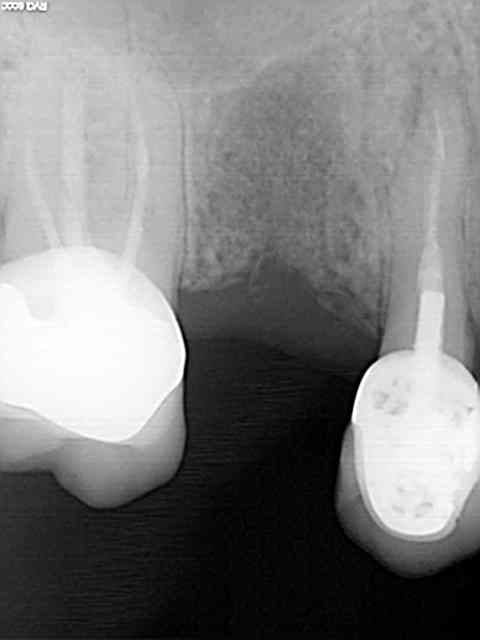

Comme promis, je donne des nouvelles de mes débuts avec le Legacy 3.

1er implant avec ce système, ce matin.

Remplacement, d'une 15 fracturée. Dent extraite en décembre 2011, attente de la cicatrisation à cause de l'infection importante autour de la dent et pose aujourd'hui d'un 3.7 longueur 10.

Quelques radios pour illustrer le cas...

Js 1 wjplje - Eugenol

Js 2 vpryz9 - Eugenol

Js 3 orny9q - Eugenol